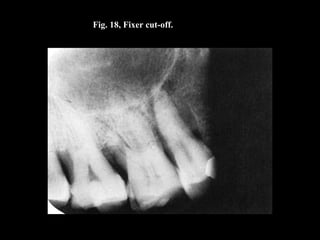

Fig. 18, Fixer cut-off.